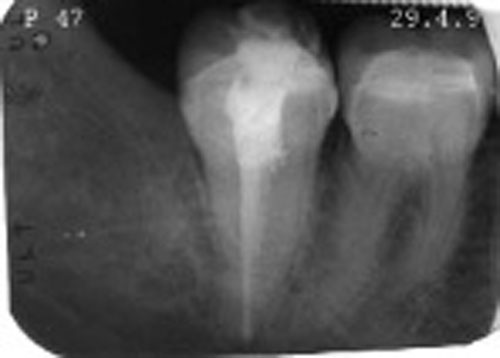

– Periapical 47

REF. 1